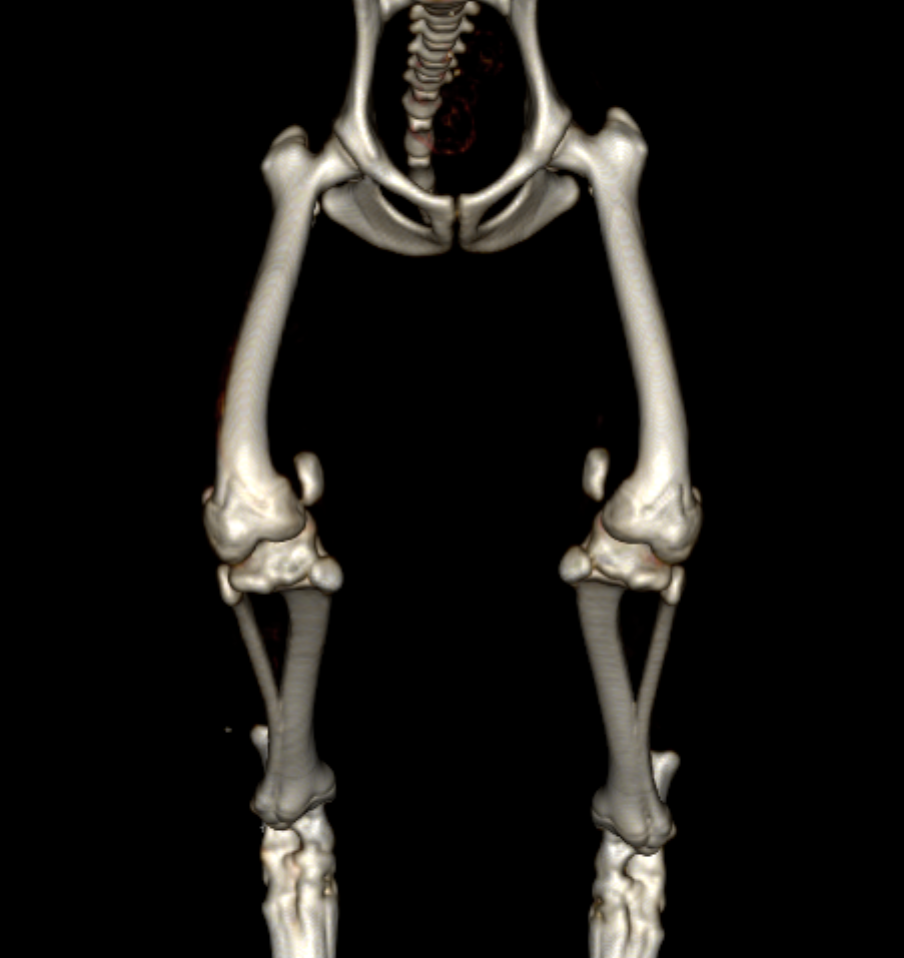

そのため、MPLグレード4の場合には手術の前にCT画像検査を実施し、大腿骨および脛骨と呼ばれる骨に変形がないかを確認します。レントゲンでも変形の評価はある程度可能ですが、3D的に変形していることが多いため、CT画像検査を実施しないと詳細がわからないことがほとんどです。

CT画像検査です。左のパテラ(向かって右側)は内側に大きく脱臼しています。この子の場合には大腿骨・脛骨共に大きな変形はないことがわかります。

この子は左右共にパテラが大きく脱臼しており、大腿骨・脛骨ともに大きく湾曲、回旋してしまっていました。